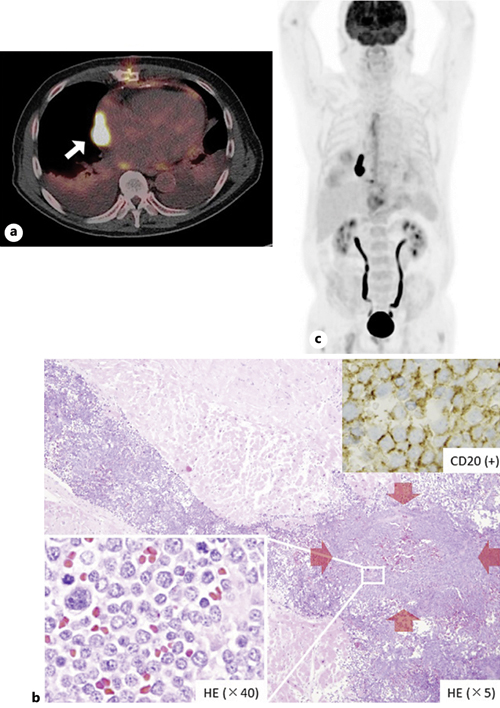

A Case Report of PostRadiotherapy cMYCPositive of the Case Reports In Oncology Karger Two case reports of resensitization to previous. Oncology | case reports in oncology | karger publishers. Goblet cell adenocarcinoma (gca) of the appendix is an uncommon type of cancer that includes both. Download our quick checklist before starting. 1 have you got everything? Case reports in oncology | karger publishers. Find more information about this subject area. Regarding positive outcomes,. Case Reports In Oncology Karger.